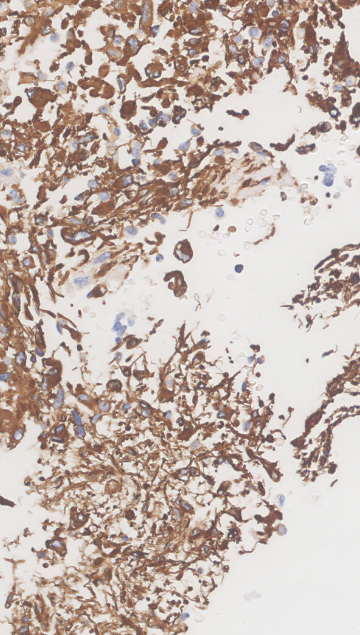

The data presented in this study have been acquired from digital images of immunohistochemistry stainings that were performed on archival tissue obtained from the neurobiobank of the Division of Neuropathology and Neurochemistry at the Medical University of Vienna. Stainings have been performed according to standard procedures (citep \@BBN(Guo et al., 2024; Schwaiger et al., 2023)). Figure 11 (a)-(c) shows a tumour biopsy of a gliosarcoma patient stained for the astrocyte marker GFAP (brown signal, cytoplasmic localization) and counterstained with Hematoxylin (blue signal, nuclear localization). Figure 3 (d)-(e) shows fetal cerebellar tissue stained for the epigenetic mark H3K27me3 (brown signal, nuclear localization) and counterstained with Hematoxylin (blue signal, nuclear localization). The stained sections have been digitalized on a NanoZoomer 2.0-HT digital slide scanner C9600 (Hamamatsu Photonics, Hamamatsu, Japan). The corresponding software NPD.Viewer2 was used to export the scanned images to tiff files. Here, we performed individual scans of a selected imaging area with different numbers of focus points. We chose either 1, 3 or 9 focus points while not changing the spatial settings for the selected field of interest. The image with 9 focus points, allowing the highest resolution, serves as the reference image.

Refer to caption

(a) Reference

(b) (18.6, 0.80, 0.10)

(c) (23.6, 0.91, 0.33)

(d) Reference

(e) (22.9, 0.81, 0.11)

(f) (27.0, 0.87, 0.22)

Figure 11: Data acquired with a slide scanner and 9 (a)(d), 3 (b)(e) and 1 (c)(f) focus points. The image with 999 focus points serves as a reference here. PSNR and SSIM misjudge the tiny spatial misalignment and therefore favor the blurry images with 1 focus point. LPIPS is able to ignore these spatial misalignments.

FR-IQA mismatches

Although the spatial settings for the selected scan area of interest were not changed during the experiment, the physical performance of the scanner showed slight spatial deviations of the selected area between individual scans and thus does not allow for high spatial accuracy during re-scanning processes. PSNR and SSIM fail to correctly assess the images in Figure 11 as they are very sensitive to that kind of misalignments. Whereas clearly the scan with 3 focus points corresponds much better to the reference as the blurred scan with 1 focus point, see (b) and (e) versus (c) and (f), both measures incorrectly judge the blurred scan as better. This wrong judgement due to a tiny spatial change is very problematic in the respective framework, as it is impossible to guarantee completely exact spatial alignment, even if no other settings had been changed during the scanning process. LPIPS is able to correctly judge the rank of quality here.